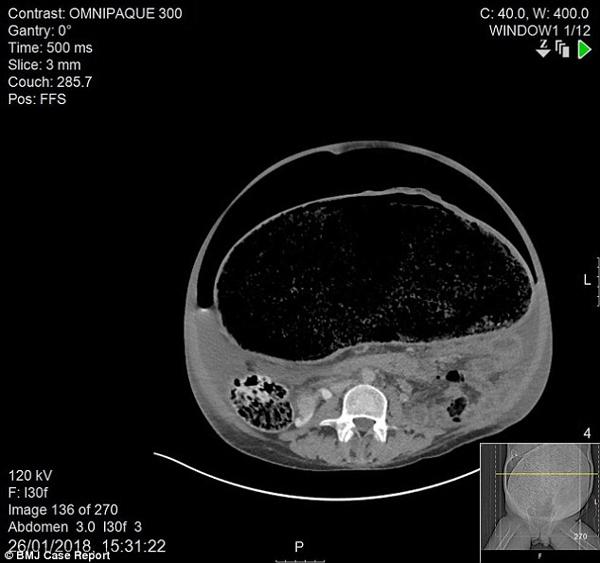

Sau khi kiểm tra tổng quát, các bác sĩ đã tiến hành chụp CT cho bệnh nhân, và nhận thấy đại tràng của anh giãn nở quá mức và bị quá tải chất thải. Các bác sĩ đã đưa cho anh thuốc nhuận tràng và thuốc xổ nhằm giúp giảm bớt tình trạng nhưng người đàn ông kiên quyết từ chối.

Các xét nghiệm sau đó cũng cho thấy thận của anh đã suy yếu, máu tăng dần độ axit. Các bác sĩ sau đó phải tiến hành chụp CT lần hai và lần này phát hiện thấy đại tràng đã bị thủng. Người đàn ông ngay lập tức được đưa đến phòng chăm sóc đặc biệt để tiến hành phẫu thuật.